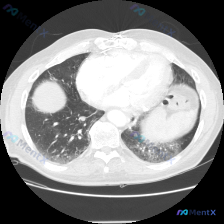

看到一个胸部CT病例,整理了一下思路。 病例资料: - CT扫描层面:心室水平层面(可见心脏、双侧下肺、部分胃泡) - 右肺:右下肺有一枚圆形结节,边缘相对光滑,密度均匀;部分区域可见散在磨玻璃密度影及轻微网格影,分布在肺外周及胸膜下 - 左肺:左下肺有较大范围病变,磨玻璃密度影与实变影混合,伴有支...